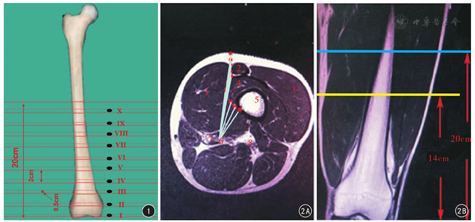

应用德国Siemens Verio 3.0 T MR仪。扫描序列及参数:轴位为脂肪抑制(fat suppression, FS)序列T2WI,TR 2 886 ms, TE 25 ms,视野160 mm×160 mm,以两侧股骨内侧髁水平线及上方18.5 cm为扫描范围,扫描厚度设定为5 mm,层间距设定为15 mm,共扫描10个层面(图1);冠状位为自旋回波(spin echo, SE)序列T1WI, TR 520 ms, TE 20 ms,视野160 mm×160 mm,层厚5 mm。收集每层大腿的轴位图像,以DICOM格式保存,传至影像存储与传输系统(picture archiving and communication systems, PACS)。将图片放大至2倍全屏调整清晰度,由3位从事临床工作5~10年的创伤骨科医师独立对各层图像,用我院PACS自带的测量工具,在轴位影像上测量各扫描层面大腿远端前内侧手术入路预计路线与股动脉之间的最短距离,即预计手术入路行进路线上的点与股动脉之间连线长度(图2A);在冠状面影像上定位该入路距离股动脉最短距离的所在平面与股骨内髁平面的距离(图2B)。若3位测量者测量值之间的差值相差较大时(差值大于10%),重新测量该数据,测量结果取3人所测得的平均值。

20例40侧受检者大腿中下段前内侧入路(预计手术行进路线)与股动脉之间最短距离MRI测量值左右两侧比较差异无统计学意义(P值均>0.05),故合并统计;两者间相距最近处位于股骨内侧髁水平线上方第Ⅵ层(股骨内侧髁水平线上方10~10.50 cm),为23.34~25.05(24.35±0.52) mm。见表1。

本研究通过MRI测量发现,前内侧入路与股血管之间(预计手术行进路线与股动脉之间)的最短距离为23.34~25.05(24.35±0.52 )mm,其所在层面位于股骨内侧髁水平线上方10~10.50 cm处,而其他层面的测量数据均大于该层面。这就表明,前内侧入路与股血管之间有一定的安全距离,沿该入路手术不会伤及股血管。Maslow和Collinge[14]通过对15例接受双侧下肢CTA检查的患者,使用二维和三维重建方法评估30个肢体,测量从股骨内侧髁远端到股动脉在股骨前缘、股骨中部和股骨后缘三点的距离分别为(27.4±3.4) cm、(22.7±3.4) cm和(18.7±4.6) cm,从股骨内侧皮质到股动脉的距离在这三点处分别为(3.3±0.8) cm、(3.1±0.8) cm和(3.1±0.9) cm。Kim等[17]通过微创接骨板固定技术,在大腿远端内侧微创治疗股骨远端骨折,并借助CTA来明确手术的安全区域,结果表明在股骨远端1/2内侧进行手术不会伤及股血管。Jiamton和Apivatthakakul[18]应用微创接骨板固定技术在10具尸体大腿远端内侧进行手术,通过CTA来测量股动脉与置入钢板之间的距离,结果表明在大腿远端60%范围内操作是安全的,股动脉不会被损伤,并且在三维重建影像资料中观察到,股动脉多在大腿近端2/5处移行到股骨内后方,因此,在股骨远端前内侧放置钢板是安全可行的。此外,采用前内侧入路进行手术时置钉方向是安全的。当内固定物安置在收肌结节前上方时,螺钉由股骨前内向后外方进入,与股血管的距离越来越远,且股骨后外侧无重要的神经血管,即使钻头进入过深、螺钉过长也不会造成血管损伤;相反采用外侧入路置入螺钉时,置钉方向由前外向后内,钻头进入过深或螺钉长度过长,均会增加损伤内侧血管的风险。